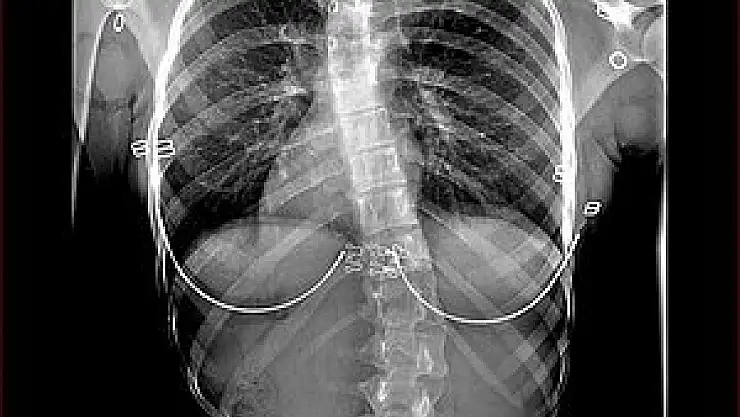

Skolyozun derecesi ve semptomlarına göre, tedavisi farklı yöntemlerle yapılabilir. Hafif skolyoz durumlarında, tedaviye ihtiyaç duyulmayabilir ve sadece düzenli takip önerilebilir. Orta veya şiddetli skolyoz durumlarında, tedaviye ihtiyaç duyulabilir. Tedavi seçenekleri arasında:

• Korse: Skolyozu önlemek veya daha fazla kötüleşmesini durdurmak için kullanılır. Genellikle çocuklarda ve ergenlerde kullanılır.

• Egzersiz ve fizyoterapi: Skolyozu düzeltmek veya semptomlarını azaltmak için egzersiz ve fizyoterapi önerilebilir. Fizyoterapi ayrıca omurganın doğru pozisyonda tutulmasına yardımcı olur.

• Cerrahi: Skolyozun ciddi dereceleri için cerrahi müdahale gerekebilir. Cerrahi müdahale, omurganın doğru pozisyona getirilmesi ve sabitlenmesi için yapılır.

Skolyoz tedavisinin başarısı, skolyozun derecesine, yaşa ve tedavinin ne kadar erken başlatıldığına bağlı olarak değişebilir. Skolyozu olan kişilerin düzenli olarak takip edilmesi ve doktorlarının önerilerine uyması önem taşımaktadır.